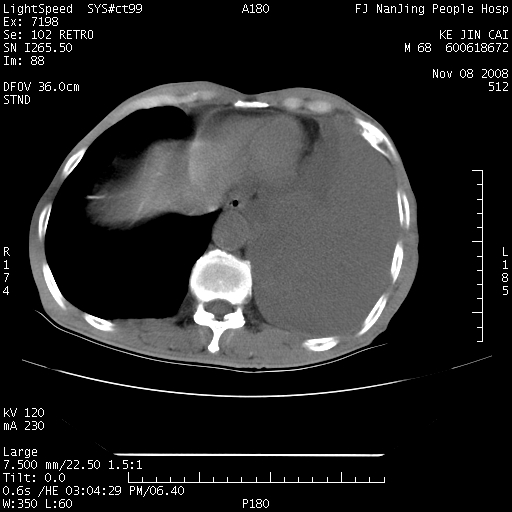

是个很有看头的病例,咋人气那么不旺?没多少人兴趣呢?这个病例几大怪:1   恶性肿瘤侵犯心肌左房怪,心肌一般不会被恶性肿瘤侵犯吧?2   左下肺均匀实变怪,内无含气,有别一般不张实变,含气肺泡完全为液体取代,而非一般不张实变的肺萎陷,冷不丁还以为是肿大的脾脏3   肿瘤本身怪,像tb肺不张4   这么有看头的病例没人气怪。呵呵。

左肺恶性肿瘤侵犯肺动脉,左心房内瘤栓,胸膜转移。

恶性肿瘤,以肺肉瘤可能大。定性诊断穿刺活检还是比较方便的。